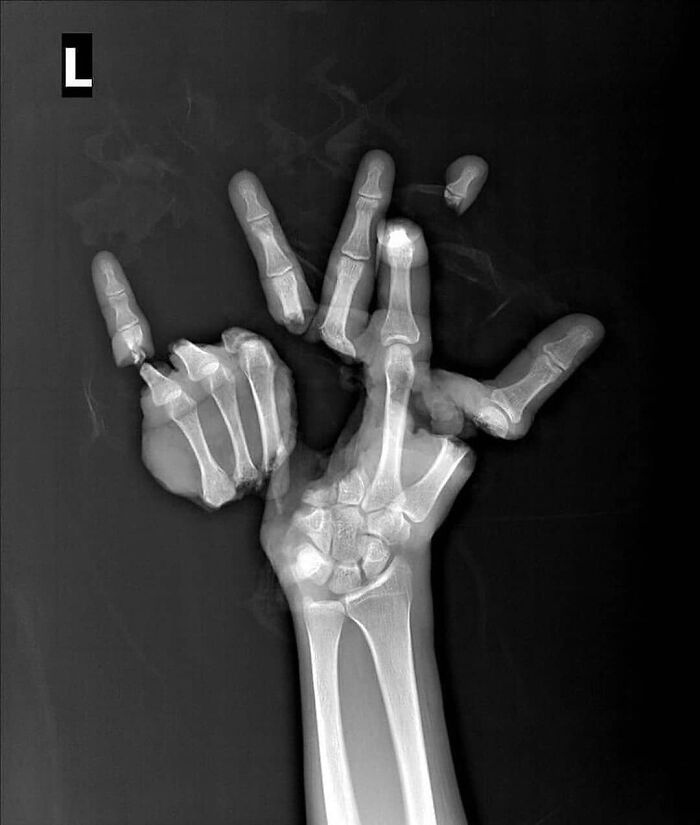

Uraz spowodowany maszyną rolniczą — wielokrotne odcięcie ręki